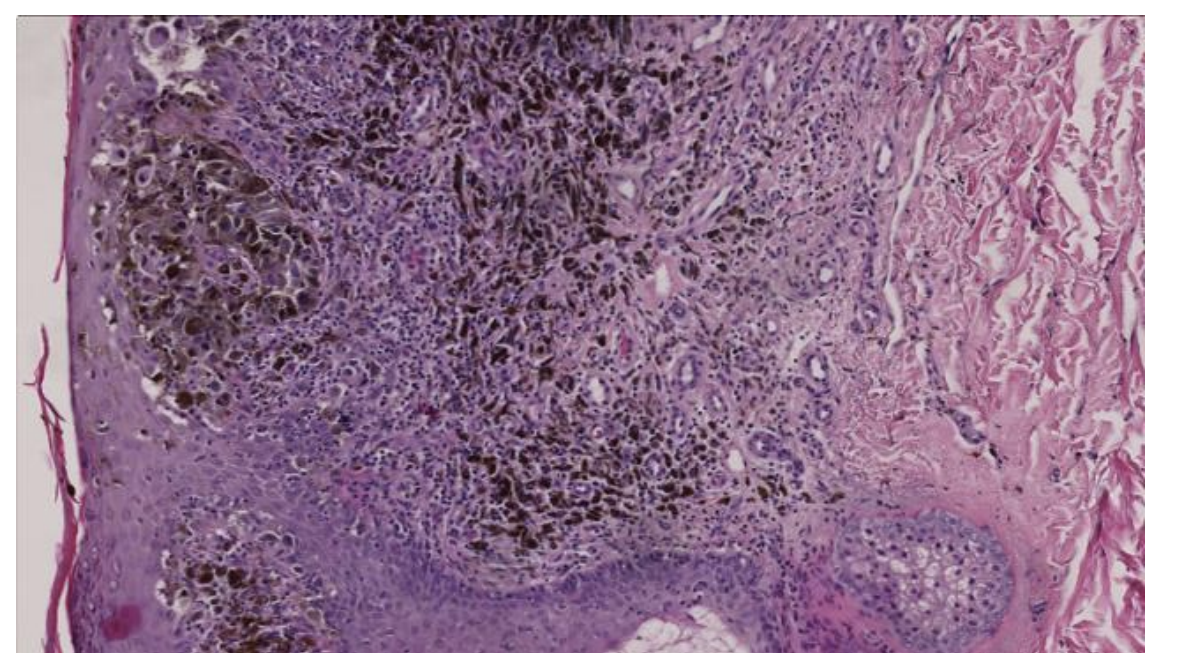

Hvilken diagnose svarer bedst til billedet?

a. Kronisk inflammation i hud

b. Planocellulært karcinom i hud

c. Tatoveringspigment i hud

d. Kulstøvsaflejring i hud

e. Malignt melanom i hud

*e. Malignt melanom i hud